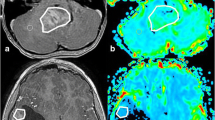

Two neuroradiologists drew the VOI that contained the solid component of whole-tumor (exclude cystic, necrotic, hemorrhagic, or blood vessel areas) on T2WI, referring to T2-FLAIR, T1WI, and CE-T1WI (3D slicer, version 4.8.1, http://slicer.org/). The ADC and CBV maps were coregistered to T2WI using SPM8 with a normalized mutual information cost function and 3rd Degree B-Spline interpolation (http://www.fil.ion.ucl.ac.uk/spm/). Then they were resampled referring to T2WI (Resample Image, 3D slicer). The VOI was moved to the ADC and CBV maps (Fig. 1). Histogram analysis was carried out using Slicer Radiomics (https://discourse.slicer.org/c/community/radiomics). All the post-processing software is open-source and easily obtained. The following features were extracted from the ADC and CBV histogram: (1) mean; (2) median; (3) 10th percentage; (4) 90th percentage; (5) interquartile range (IQR); (6) kurtosis, which is a metric of the degree of peakedness of a distribution; (7) skewness, which could describe the degree of asymmetry of a distribution; (8) entropy. The relative value of all quantitative MR parameters was calculated by dividing the value of the tumor by the reference value of the contralateral normal-appearing white matter. The time required for the whole-tumor histogram analysis method was 210.35 ± 33.88 s.

According to the T2WI, T1WI, CE-T1WI, and T2FLAIR images (a-d), the VOI of the solid component (the yellow area) is drawn on T2WI (e) (exclude cystic, necrotic, hemorrhagic, or blood vessel areas, the green area) and registered to the ADC (f) and CBV images (g). The three-dimensional image of tumor segmentation is demonstrated on (h)